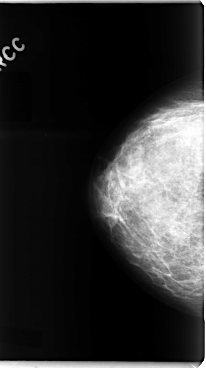

C_0091_1.RIGHT_CC

C_0091_1.LEFT_CC

LEFT_CC LINES 4744 PIXELS_PER_LINE 2664 BITS_PER_PIXEL 12 RESOLUTION 50 OVERLAY

RIGHT_CC LINES 4776 PIXELS_PER_LINE 2672 BITS_PER_PIXEL 12 RESOLUTION 50 NON_OVERLAY

FILE: C_0091_1.LEFT_CC.OVERLAY

TOTAL_ABNORMALITIES 1

ABNORMALITY 1

LESION_TYPE MASS SHAPE IRREGULAR MARGINS SPICULATED

ASSESSMENT 5

SUBTLETY 5

PATHOLOGY MALIGNANT

TOTAL_OUTLINES 1

BOUNDARY